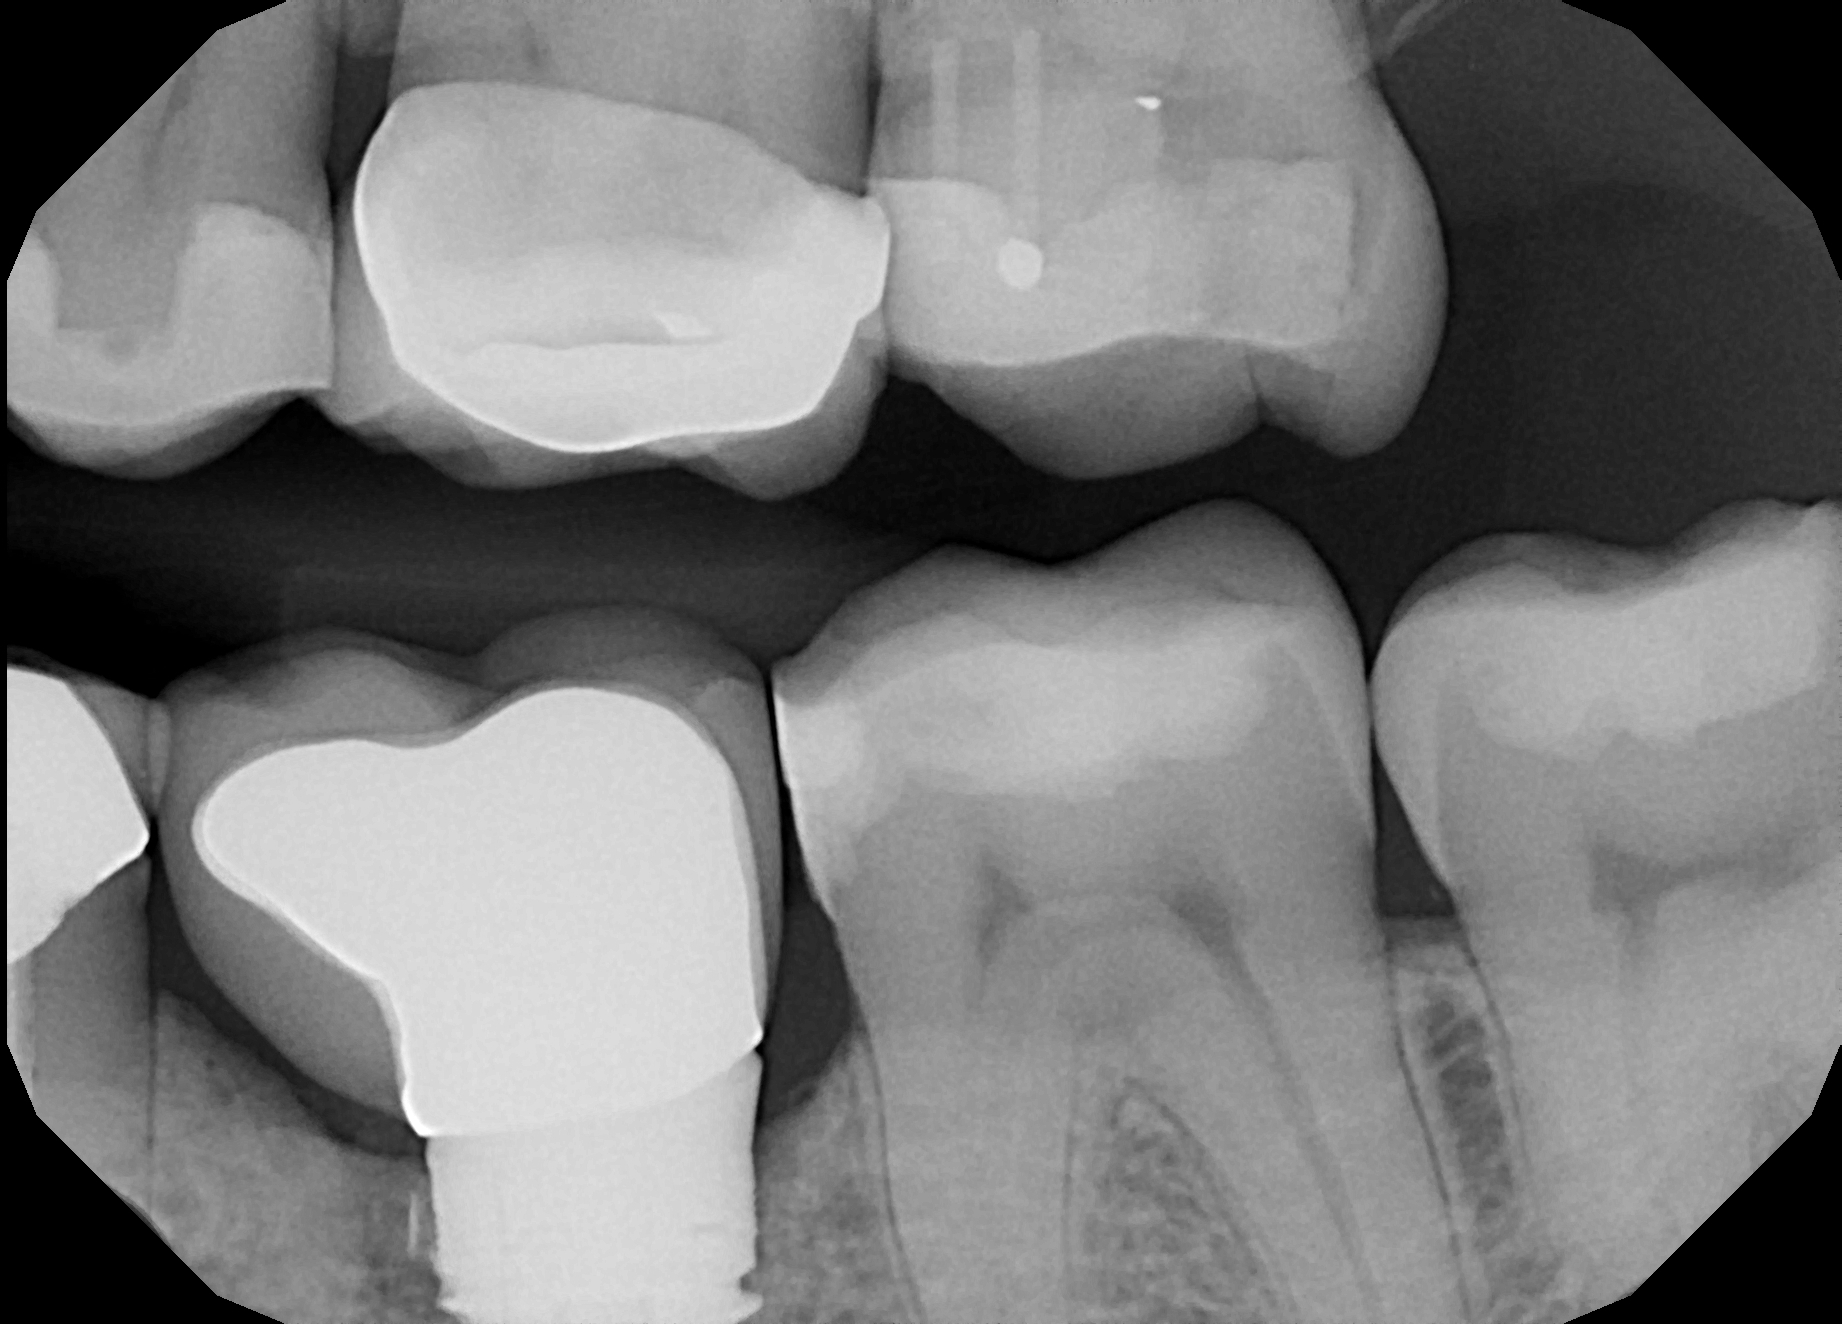

Posterior DentXpinTM repair.